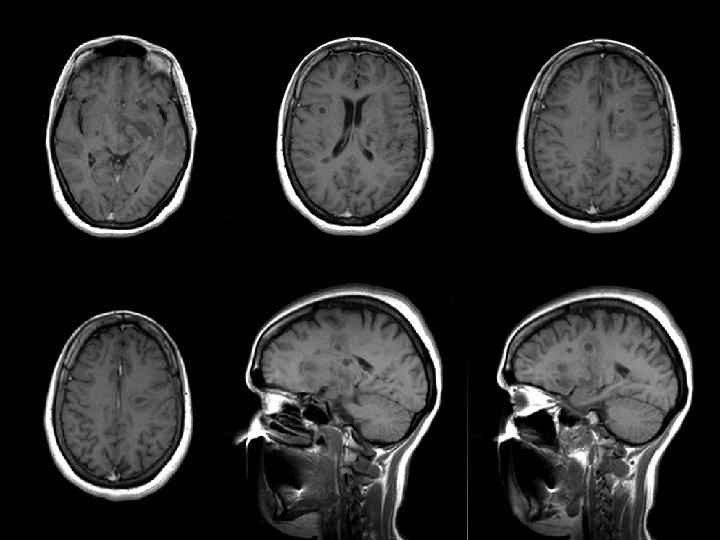

q IRM: d’hpersignaux sub blanche. Sur les séquences pondérées en T 2, les images ne sont pas spécifiques mais leur répartition et leur aspect évoquent des lésions de démyélinisation. Péri ventriculaire, en sub blanche profonde. Arrondies ou ovalaire, taille variable: qlq mm à qlq cm. Evocatrices en péri ventriculaire, sus tensorielle, médullaire.

Séquence T 1 après injection de Gadolinium st informative, les lésions rehaussées/Gado st évolutives. L’hyper signal induit /Gado est svt annulaire en périphérie de la lésion.

SEP Dissémination dans l’espace IRM: lésions multiples et sans R/ avec la symptomatologie apportée. La présence d’au moins 4 lésions dont 1 péri ventriculaire est significative. Dissémination dans le temps Aspect différent de lésions mais surtout le rehaussement de certaines d’entre elles témoignant de lésions d’ages différents.

Figure 1. IRM en séquence T 1 : « trous noirs » dans la substance blanche

Figure 3. IRM en séquence T 1 avec injection de gadolinium : lésions périventriculaires.